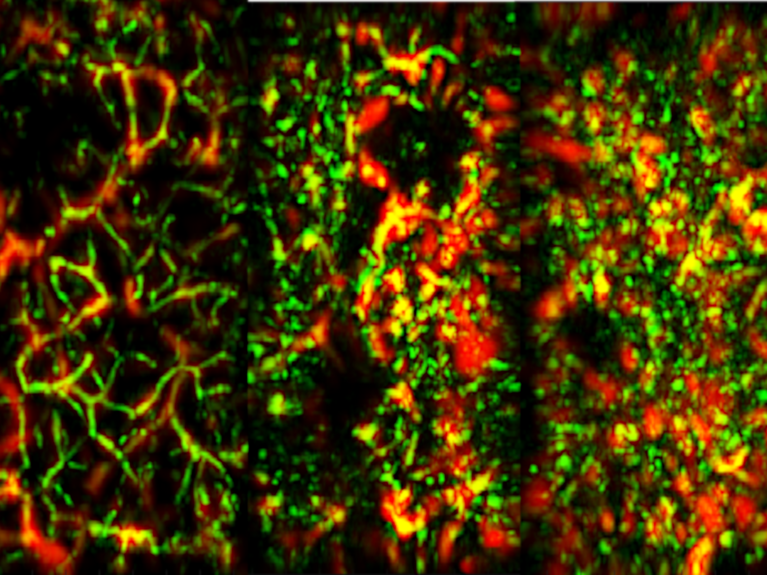

Basierend auf der Optoakustik haben Wissenschaftler:innen bei Helmholtz Munich ein neues Verfahren eingeführt, das kontrastreiche, hochauflösende Bilder erzeugt. Es ist kostengünstig und sicher, kommt ohne Kontrastmittel aus und kann die Diagnostik in die Arztpraxis und sogar nach Hause bringen, um Krankheiten frühzeitig zu erkennen.

Bild: Hailong He/ Helmholtz Munich